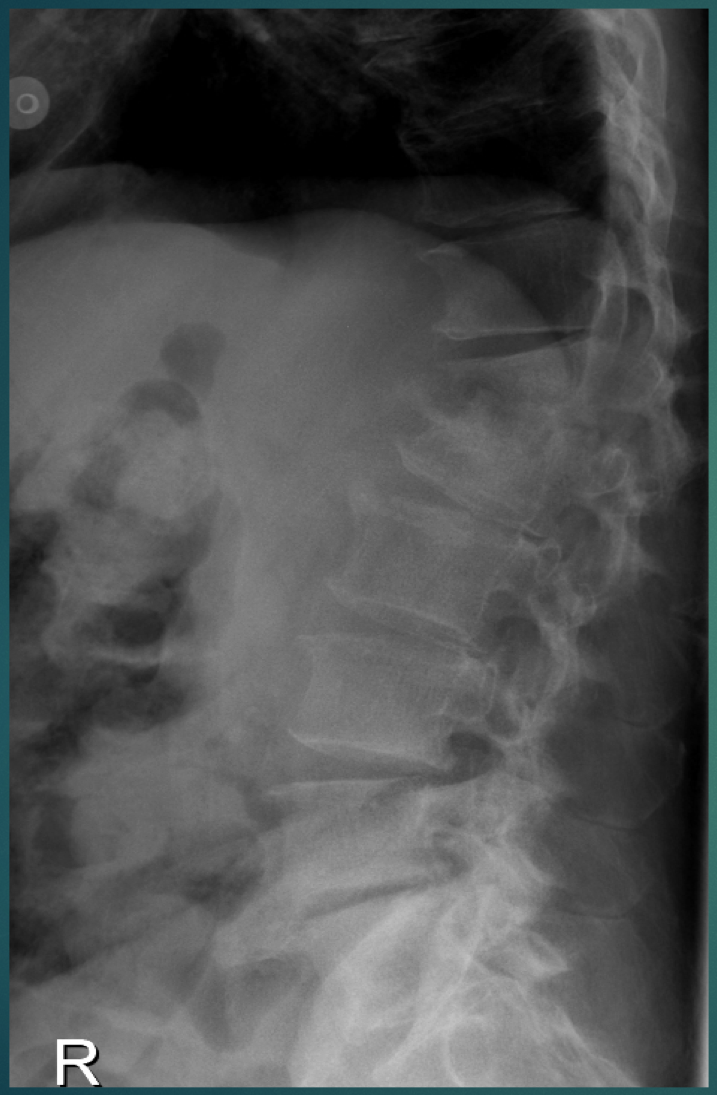

32 YO M. Several months of back pain.

• Endplate destruction

• Loss of disc height /space

• Acute kyphosis at the 2 segments (might look like retrolisthesis)

Think: infectious discitis